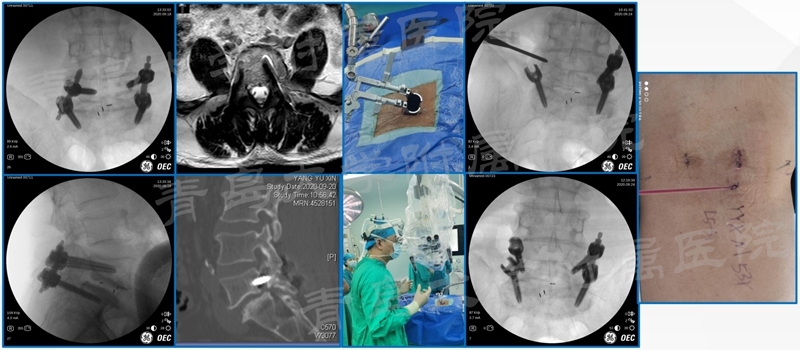

临床资料

回顾性分析了2019年7月至2022年4月期间52例术前或术后符合足下垂诊断标准的脊柱手术患者;记录患者平均年龄、术前诊断、发生足下垂的时间、手术方式、手术时间、住院时间、卧床时间及术后康复时间;患者随访至少24个月。术前、术后1周、术后3个月、6个月、12个月、术后24月分别评估SF-36、Oswestry残疾指数(ODI)评分及下肢肌力评定。

患者平均年龄48.1岁;52例出现足下垂;明确L5神经根受压者42例(80.8%)。术前即出现者28例(53.8%);26例恢复时间1周-2年;2例未恢复;术后神经功能加重9例(17.3%);1例1周恢复,2例1月,3例3月,1例24月;2例未能恢复。马尾综合征致足下垂者4例,1例未能完全恢复;术后血肿压迫者2例,术后1例1周恢复,另1例术后3月恢复;内镜手术后复发者1,术后10月恢复;开放腰椎术后2例,恢复时间6月;内固定者失败者2例,1例3月恢复,1例未恢复;术后各种原因致加重9+7=16例(30.8%);胸椎2例,平均恢复时间3月;颈椎1例,恢复时间6月。

典型案例

案例一

案例二

案例三

椎弓根螺钉进入椎管卡压L5神经根